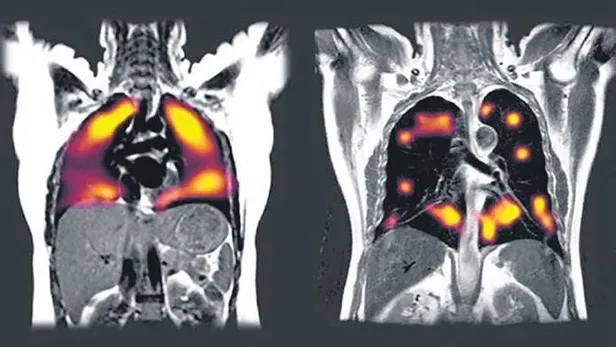

CİĞERLERİ BÖYLE BİTİRİYOR

Oxford Üniversitesi, COVİD-19'un akciğere etkisini araştırdı. Solda, sağlıklı akciğerde kanın nasıl dolaştığı gözlenirken, sağda Coronavirüs'e yakalanan hastanın ciğerleri simsiyahtı.